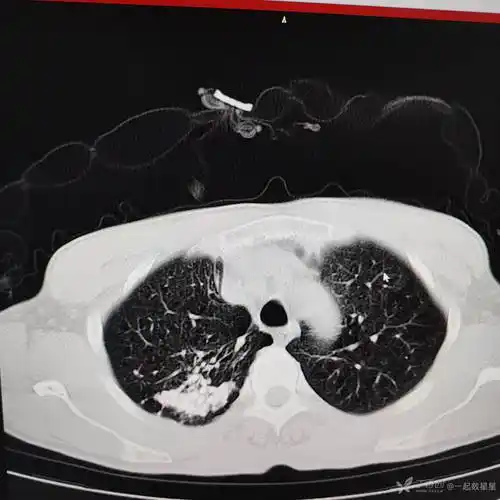

ct显示双肺有多发性钙化病变.

右肺中,下叶斑块状,条索状病灶,内有钙化灶番茄医生提醒,运用b超或ct

肺部点状钙化影

肺内钙化病灶的鉴别诊断

肺内多发钙化灶考虑什么

请问这样的ct片子是不是说明肺结核已经钙化了?